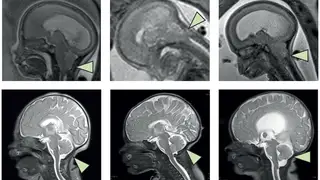

La flecha señala el rombencéfalo, la región del cerebro vinculada a la hormonaThe LancetThe Lancet

La hormona, conocida como FGF21 (factor de crecimiento de fibroblastos 21), ya ha despertado interés como posible objetivo para nuevas terapias y actualmente se está probando en ensayos clínicos fármacos diseñados para actuar sobre esta vía para la esteatohepatitis asociada a disfunción metabólica (MASH), una forma grave de enfermedad del hígado graso. El equipo de Potthoff se centró en comprender cómo la FGF21 produce sus efectos. Sus resultados muestran que la hormona actúa a través del rombencéfalo, ubicado en la parte inferior posterior del cerebro.

“En nuestros estudios previos, habíamos observado que el FGF21 envía señales al cerebro en lugar de al hígado, pero desconocíamos su ubicación exacta - explica Potthoff en un comunicado -. Pensábamos que enviaría señales al hipotálamo (que participa activamente en la regulación del peso corporal), por lo que nos sorprendió descubrir que la señal se dirigía al rombencéfalo, donde se cree que actúan los análogos del GLP-1”.

Más específicamente, el FGF21 interactúa con dos partes del rombencéfalo: el núcleo del tracto solitario (NTS) y el área postrema (AP). Estas regiones se comunican con otra estructura cerebral conocida como núcleo parabraquial. Esta cadena de señalización es esencial para que la hormona pueda influir en el metabolismo y reducir el peso corporal.